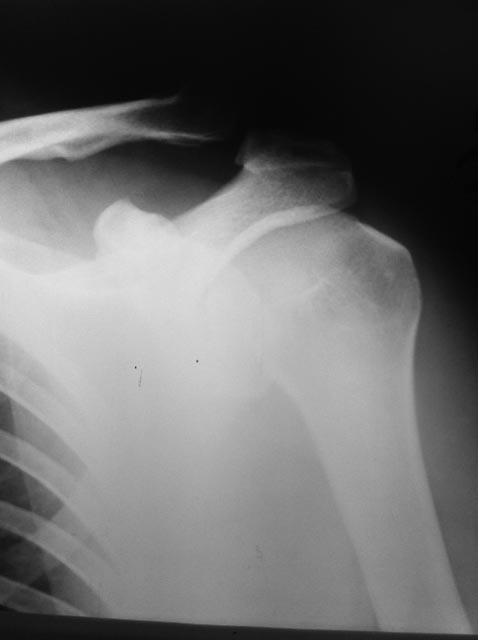

Травма в результате падения на лыжах 4.01.2013Мнения коллег разошлись.Стоит

оперироваться или можно обойтись консервативно?